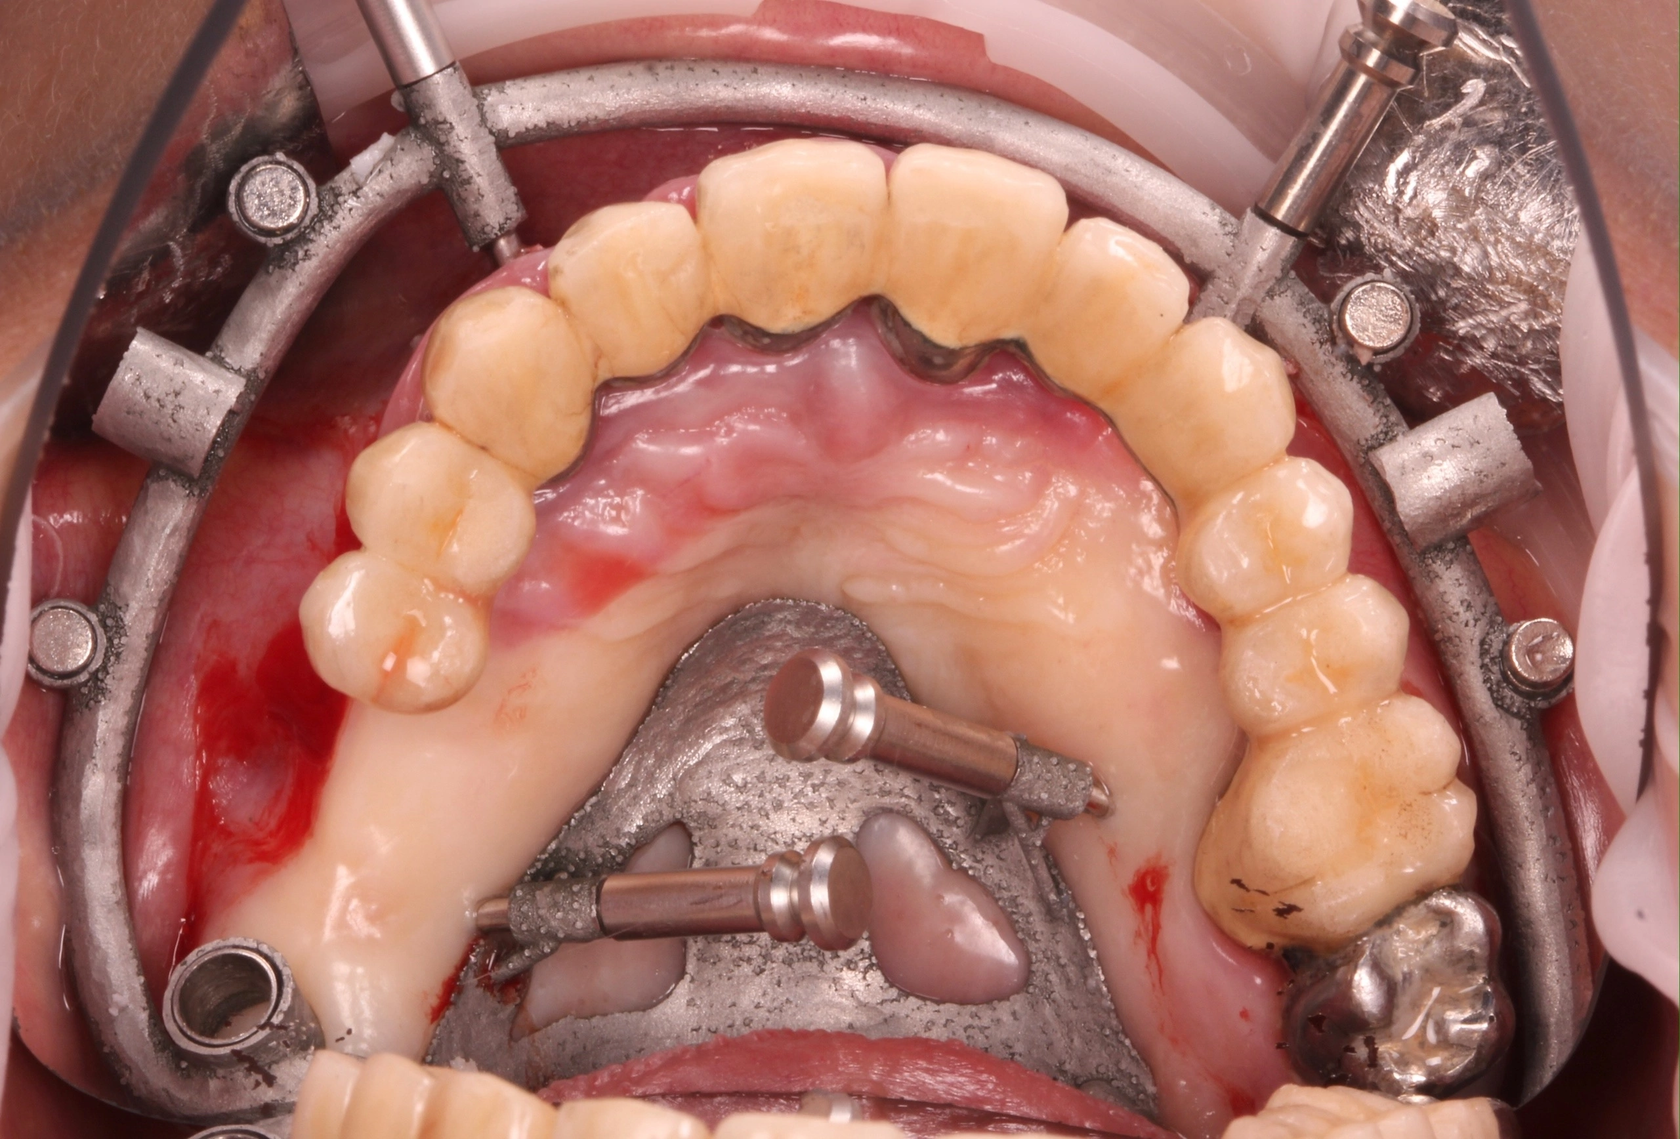

7. Выбор стратегии и моделирование хир. шаблона 5 стратегий: - Шаблон с опорой на зубы - Шаблон с опорой на слизистую - Шаблон с опорой на кость - Последовательные шаблоны с опорой на костные пины - Разборный шаблон Результат: STL файл хир. Шаблона и отчет в PDF

9. Особенности хирургического этапа - Формирование лоскутов - Контроль качества посадки - Отклонение фрезы - Ложный торк

10. Возможность изготовления префабрикованных конструкций. - Готовые одиночные конструкции - Конструкции под вклейку/перебазировку - Сварка опорной титановой балки - Прототипы тотальных работ

Учебный проект 1 - Накостный шаблон из металла

Клинические особенности применения накостного шаблона